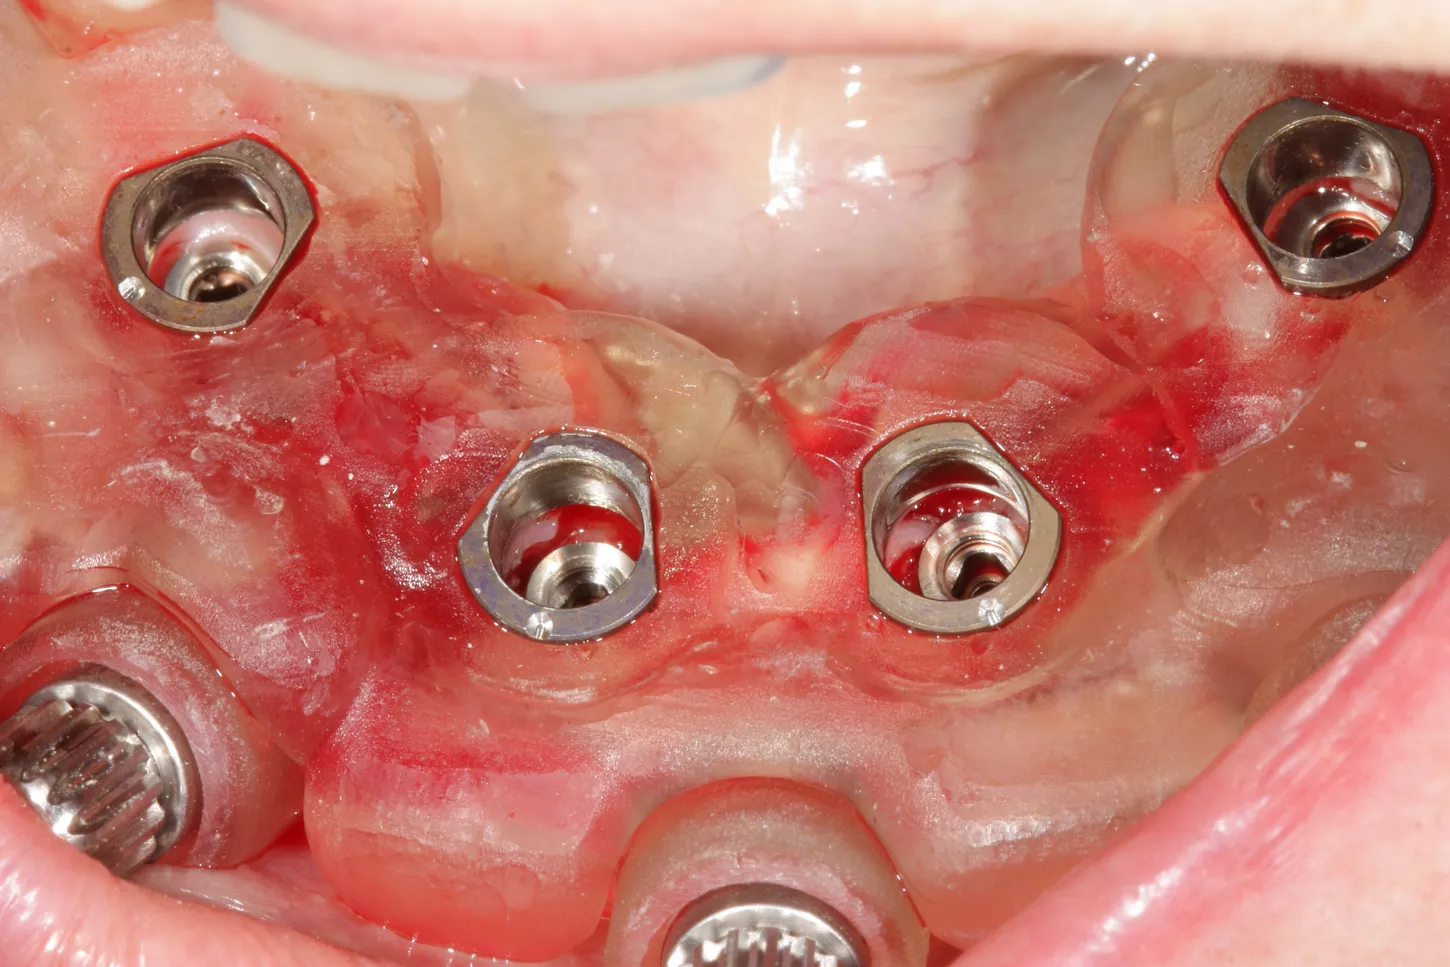

8. Implants are in situ; the procedure was minimally invasive.

9.  Positioning of the Tissue Level temporary abutments platform N plural reference number TC100-N-P to accommodate the prefabricated temporary restoration.